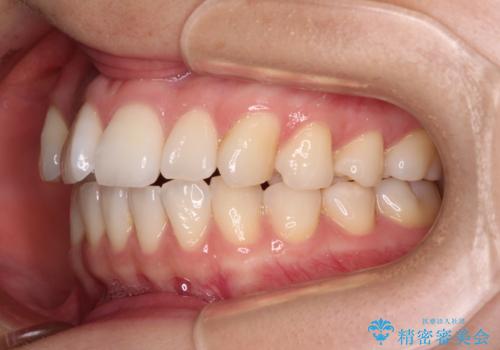

前歯のデコボコと口元の膨らみを治したい ワイヤー装置での非抜歯矯正

- 前歯のデコボコと、上下前歯が接触せずに前に飛び出していることを気にして来院された患者様です。

舌の突出癖が強く、それが原因で上顎歯列全体が前方に突出し、上下前歯が接触できない状態となっていました。

舌のトレーニングは不十分でしたが、1年半ほどで治療を終えることができました。